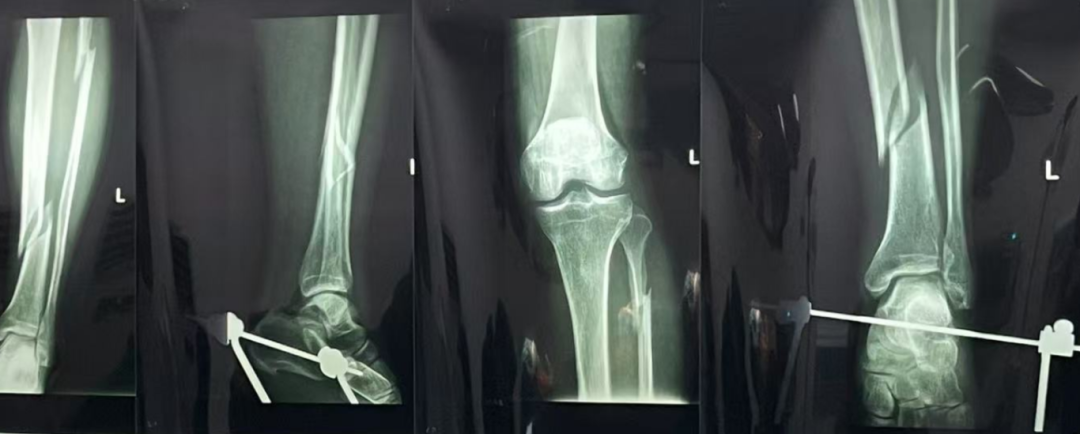

王女士,28岁,因遗传+长期穿高跟鞋导致踇外翻,外翻角度超40°,伴有疼痛和行走困难。她因工作需要,希望尽快手术。李龙飞医生评估后,决定采用微创手术,并制定详细术前准备和术后康复计划。手术顺利,王女士恢复良好,工作前已能正常行走,疼痛减轻。她感激地说:“李医生不仅治愈了我的脚,更让我在重要时刻能够自信地站出来。”

十多年的临床经验,让李龙飞医生在面对疑难病例时更加从容自信。他深知,足踝疾病的复杂机制和病因常常干扰医生的判断,但只要明确治疗诉求,逐步分析问题,就能找到解决问题的关键。这种临床思路和决策能力,不仅帮助他成功治愈了众多患者,也为他在骨科领域赢得了极高的声誉。